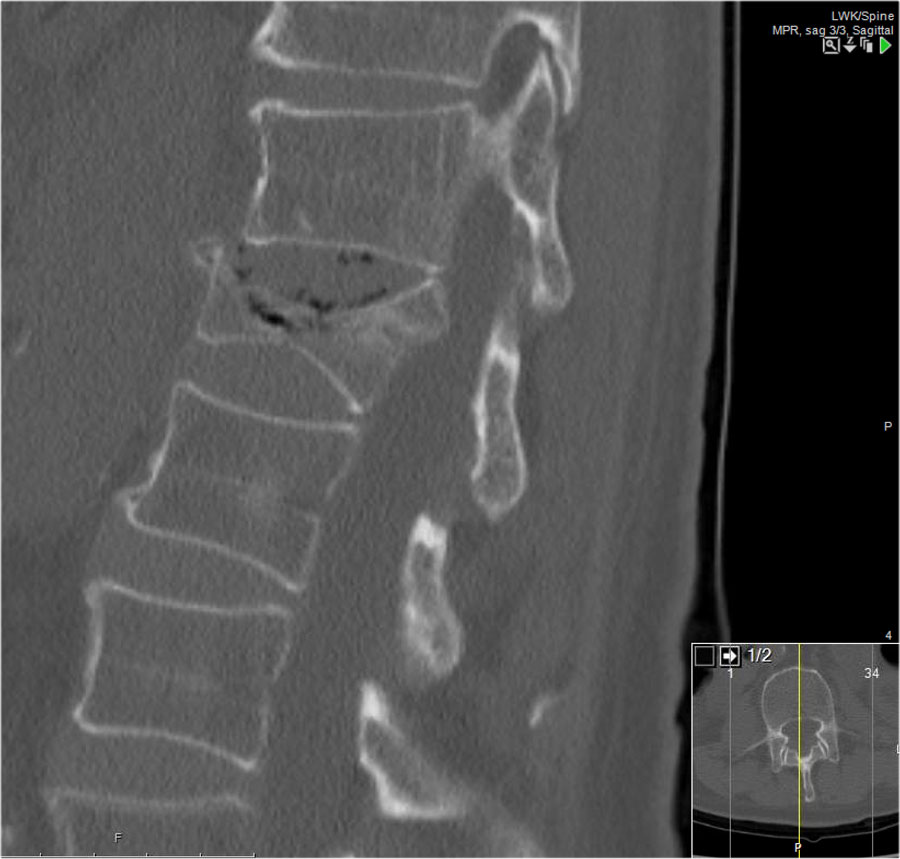

Các hình ảnh là của một bệnh nhân với hình ảnh cột sống tre điển hình do viêm cột sống dính khớp.

Sau khi ngã ngửa, không thấy gãy xương trên phim X-quang.

Tuy nhiên, CT cho thấy một đường gãy mảnh qua mặt trước thân đốt sống và cả qua mỏm gai.

Tiếp tục xem các hình ảnh MRI.